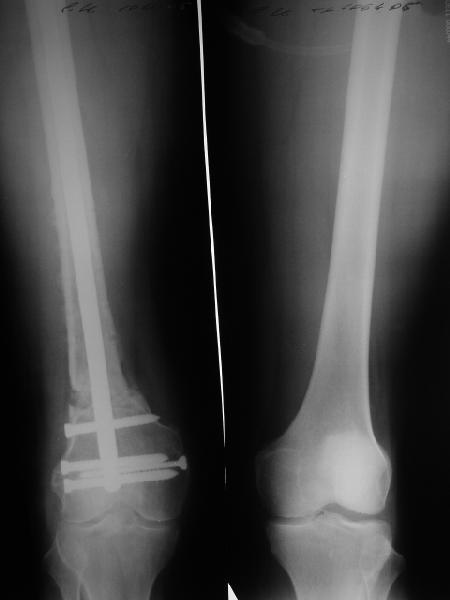

Пациенту М., 30-ти лет, 1,5 года назад в одной из московских больниц был выполнен остеосинтез бедренной кости штифтом UFN (диаметр штифта 9 мм).

К нам больной поступил с признаками ложного сустава бедренной кости, перелома

штифта и дистального блокирующего винта (images 1,2,3).

27 марта выполнено удаление блокирующих винтов (сломанный винт пришлось высверливать цапфен-бором), сломанного штифта (дистальный фрагмент удален через канал, образованный разверткой из коленного сустава - image 4),

рассверливание костно-мозгового канала, реостеосинтез штифтом UFN (при проведении штифта в дистальном отломке мы использовали поляризующий винт, диаметр штифта 10 мм). После операции в связи гемартрозом дважды (на 1 и 3 сутки) выполняли пункцию коленного сустава. Сейчас признаков скопления жидкости в полости сустава нет. Послеоперационные рентгенограммы - images 5, 6, 7.